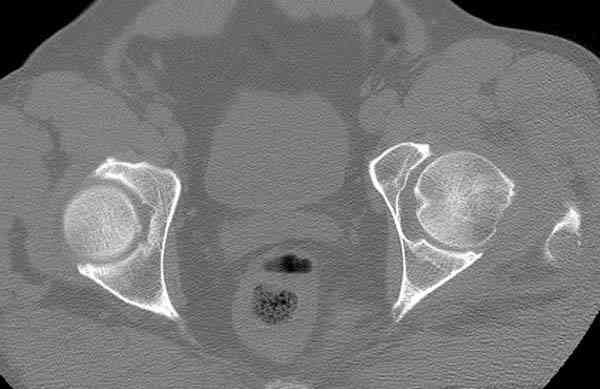

Кроме обязательных ренгенологических снимков тазобедренного сустава, при подозрении на перелом шейки рекомендуем Компьютерную Томографию.

Года два назад в ОТА из группы Торнетта было доложено о "missed femoral neck fractures" даже после КТ исследования.

После интрамедуллярного остеосинтеза бедра, по нашему протоколу, описываем состояние шейки и обязательный контрольный снимок шейки.

Недавно у нас тоже был случай, узнали на второй день после осмотра протокольных снимков шейки.

сделаны Компьютерная Томограмма